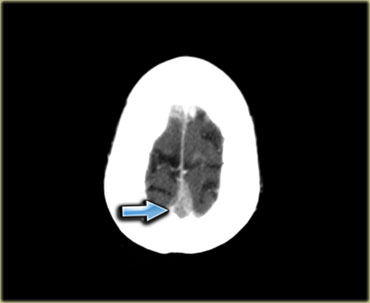

Nhồi máu tĩnh mạch (3) – Tĩnh mạch Labbe

Một dạng nhồi máu tĩnh mạch điển hình khác là do huyết khối tĩnh mạch Labbe.

Hình ảnh bên trái cho thấy giảm tỷ trọng ở chất trắng và ít rõ hơn ở chất xám của thùy thái dương trái.

Chẩn đoán phân biệt rộng bao gồm nhồi máu động mạch, nhiễm trùng, u não, v.v.

Lưu ý có một số đường tăng tỷ trọng trong vùng nhồi máu.

Đây là do xuất huyết.

Trong chẩn đoán phân biệt, cũng cần xem xét nhồi máu tĩnh mạch trong vùng phân bố của tĩnh mạch Labbe.

Tỷ trọng tăng nhẹ ở vùng xoang ngang trái (mũi tên) là chìa khóa để chẩn đoán.

Đây là dấu hiệu trực tiếp của huyết khối và bước tiếp theo là chụp CECT, xác nhận chẩn đoán (không hiển thị).